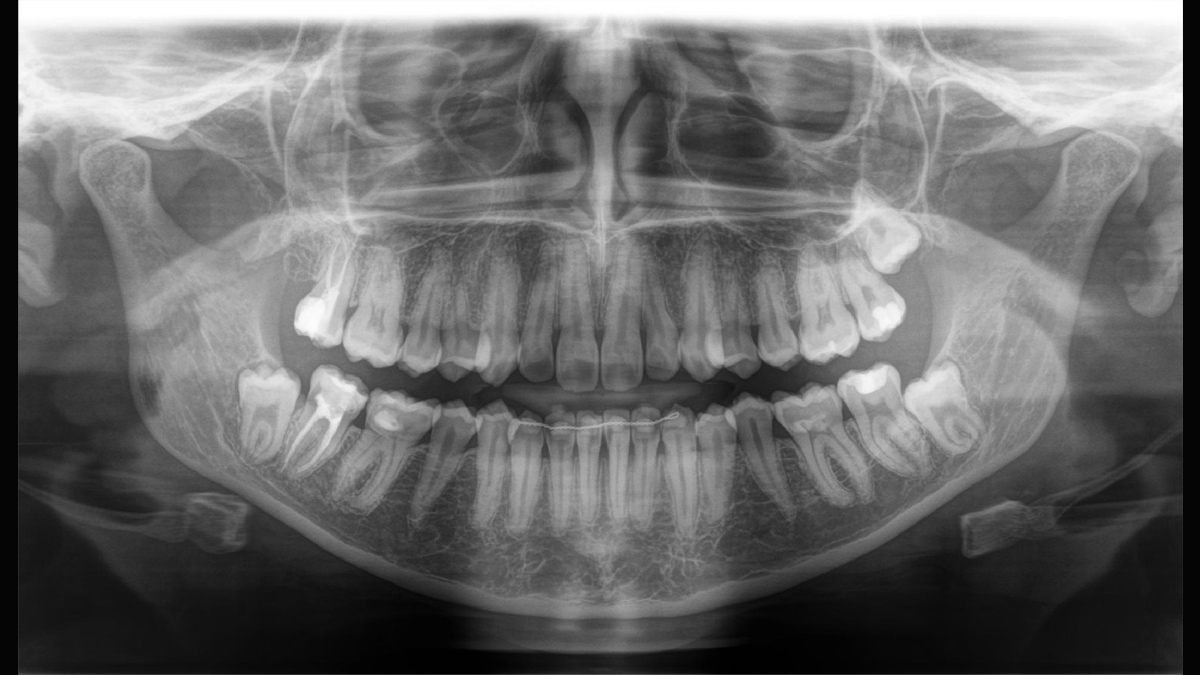

Aunque las radiografías 3D son cada vez más demandadas y existen un gran un número creciente de equipos en consultorios dentales, la imagen 2D sigue teniendo su lugar, en gran medida, debido a su radiación. Las mejoras realizadas en la calidad de imagen hace que las opciones disponibles en tecnología 2D están lejos de haberse agotado. Orthophos SL ha revolucionado la imagen 2D con la introducción del Sensor de Conversión Directa, la tecnología Sharp Layer y la SL interactiva. Experimente imágenes panorámicas como nunca antes.

Galería de muestra de imágenes panorámicas 2D